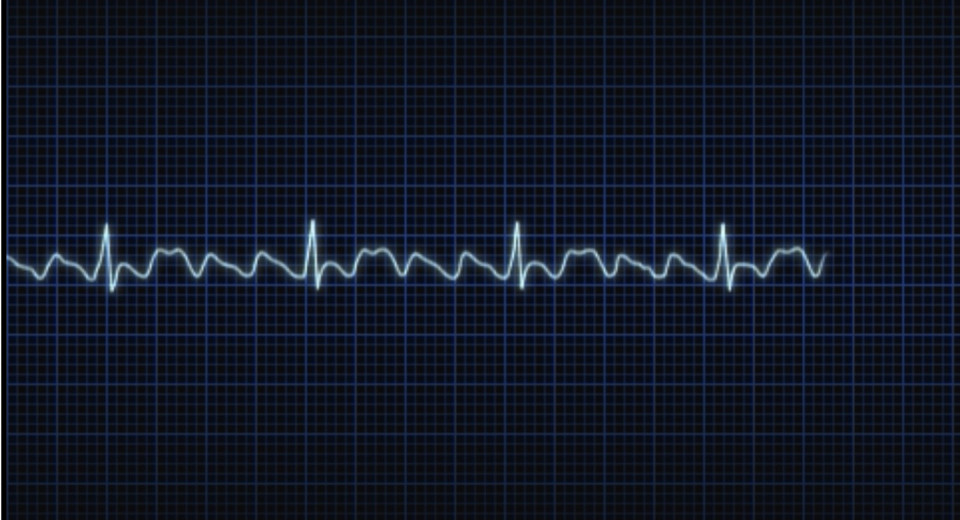

低血糖の症状は、冷や汗、動悸、息切れなど

徴候には、低血圧、頻脈、蕁麻疹、血管性浮腫、呼気性喘鳴、吸気性喘鳴、チアノーゼ、および失神などがある。数分以内に死亡することがある。

少女の症状

発汗

蕁麻疹

喘鳴(気道閉塞)

チアノーゼ

血圧低下など